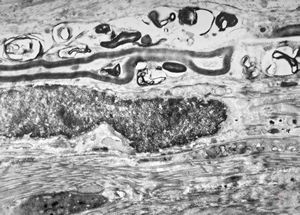

M,13y. | - n.suralis - hypertrophic demyelinizing neuropathy

n.suralis - hypertrophic demyelinizing neuropathy